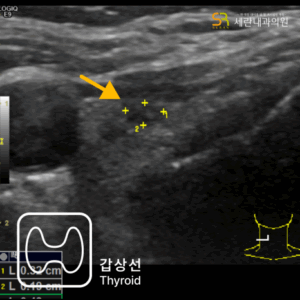

가스 차는 증상과 경미한 혈변으로 발견된 직장암 사례설사와 혈변, 항문 통증으로 내원했다가 직장암을 진단받은 40대 남성 사례심한 변비로 내원하여 상행결장암을 진단받은 80대 남성 사례속쓰림으로 내원했다가 복부초음파로 조기 담낭암을 발견한 사례명치 통증과 소화불량으로 내원했다가 췌장암 3기가 진단된 사례무증상 검진 중 갑상선초음파로 발견된 조기 갑상선 유두암 사례유방 통증으로 내원했다가 유방초음파로 조기 진단된 침윤성 유방암 사례명치 통증으로 내원했다가 진행성 위암을 발견한 60대 여성 사례속쓰림으로 내원했다가 signet ring cell type 위암을 조기 발견한 60대 여성 사례소화불량으로 내원했다가 작은 조기 위선암을 발견한 50대 여성 사례변비로 내원했다가 침윤성 궤양 형태의 위암을 발견한 70대 여성 사례소화불량으로 내원했다가 진행성 위암을 발견한 60대 여성 사례경미한 속쓰림으로 방문했다가 조기 위선암을 발견한 60대 여성 사례가스 차는 증상과 경미한 혈변으로 발견된 직장암 사례설사와 혈변, 항문 통증으로 내원했다가 직장암을 진단받은 40대 남성 사례심한 변비로 내원하여 상행결장암을 진단받은 80대 남성 사례속쓰림으로 내원했다가 복부초음파로 조기 담낭암을 발견한 사례명치 통증과 소화불량으로 내원했다가 췌장암 3기가 진단된 사례무증상 검진 중 갑상선초음파로 발견된 조기 갑상선 유두암 사례유방 통증으로 내원했다가 유방초음파로 조기 진단된 침윤성 유방암 사례명치 통증으로 내원했다가 진행성 위암을 발견한 60대 여성 사례속쓰림으로 내원했다가 signet ring cell type 위암을 조기 발견한 60대 여성 사례소화불량으로 내원했다가 작은 조기 위선암을 발견한 50대 여성 사례변비로 내원했다가 침윤성 궤양 형태의 위암을 발견한 70대 여성 사례소화불량으로 내원했다가 진행성 위암을 발견한 60대 여성 사례경미한 속쓰림으로 방문했다가 조기 위선암을 발견한 60대 여성 사례

30년 경력 의료진의 판독,

세란의 초음파 클리닉

내과·영상의학과 전문의가

직접 검사부터 판독까지

30년 경력의 영상의학과

의료진이 함께하는 신뢰도 높은 진단

당일 검사, 당일 결과 확인 가능합니다.